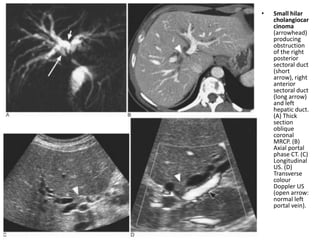

• Small hilar

cholangiocar

cinoma

(arrowhead)

producing

obstruction

of the right

posterior

sectoral duct

(short

arrow), right

anterior

(long arrow)

and left

hepatic duct.

(A) Thick

section

oblique

coronal

MRCP. (B)

Axial portal

phase CT. (C)

Longitudinal

US. (D)

Transverse

colour

Doppler US

(open arrow:

normal left

portal vein).

• Small hilar cholangiocar cinoma (arrowhead) producing obstruction of the right posterior sectoral duct (short arrow), right anterior sectoral duct (long arrow) and left hepatic duct. (A) Thick section oblique coronal MRCP. (B) Axial portal phase CT. (C) Longitudinal US. (D) Transverse colour Doppler US (open arrow: normal left portal vein).